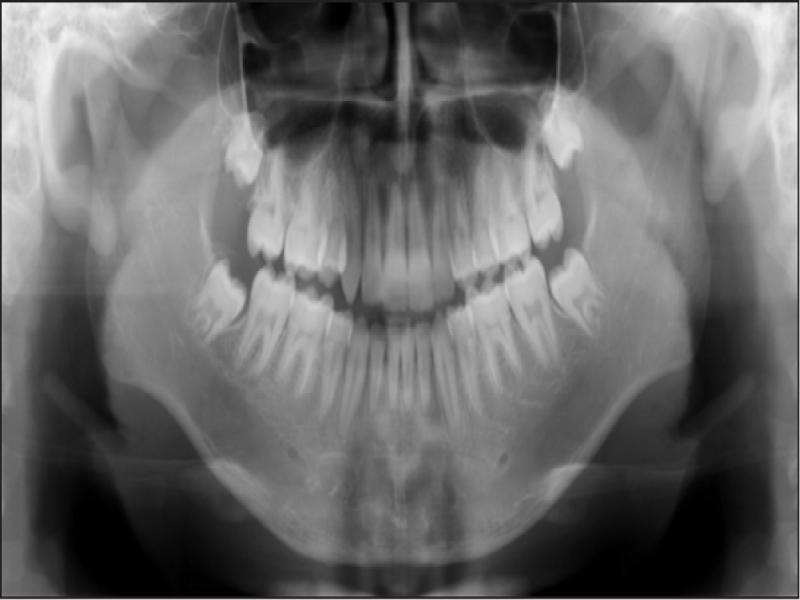

Treatment was initiated after the extraction of the recommended teeth. Banding and bonding were completed using 0.018″ × 0.025″ brackets of Roth prescription. Both arches were levelled and aligned using 0.014″ nitinol wire. The wires were upgraded to 0.016″ stainless steel wires, and power chains were used to retract the upper right canine and consolidate the lower canine-to-canine region to prepare for lower en masse retraction. After the lower anterior spaces were closed, a 0.016″ × 0.022″ nitinol wire with a reverse curve was inserted. The lower canine-to-canine region and the lower first molar to second premolar on both sides were consolidated using a stainless steel ligature wire, and a power chain was stretched from the lower second premolar to the lower canines. Due to its long root, a prefabricated upper lip bumper was inserted to reinforce upper arch anchorage during upper right canine retraction (Figure 4). Once the upper right canine was retracted, the upper lip bumper was removed, and an upper 0.016″ × 0.022″ stainless steel wire with keyhole loops was activated to retract the upper incisors. Palatal root torque was added to achieve bodily retraction of the upper incisors. After all space closure, upper and lower 0.016″ × 0.022″ nitinol wires were placed followed by 0.016″ × 0.022″ stainless steel wires for finishing and detailing using class II elastics as needed. To improve the aesthetics of the upper left first premolar, labial root torque was applied along with enameloplasty of the palatal cusp. Interproximal reduction of the upper incisors was performed to manage a Bolton discrepancy and improve overjet and overbite. Because fixed retainers were refused by the patient’s mother, modified upper and lower Hawley retainers were provided for retention. The patient was referred for aesthetic restoration of the upper right canine but chose not to proceed. The total treatment time was two years and eight months (Figures 5–8; Table I). Figure 9 shows images of the patient 19 months after active treatment. The result remained stable except for some extraction space opening distal to the lower canines.

Panoramic radiograph taken at the debond visit (age 15 years, 3 months).